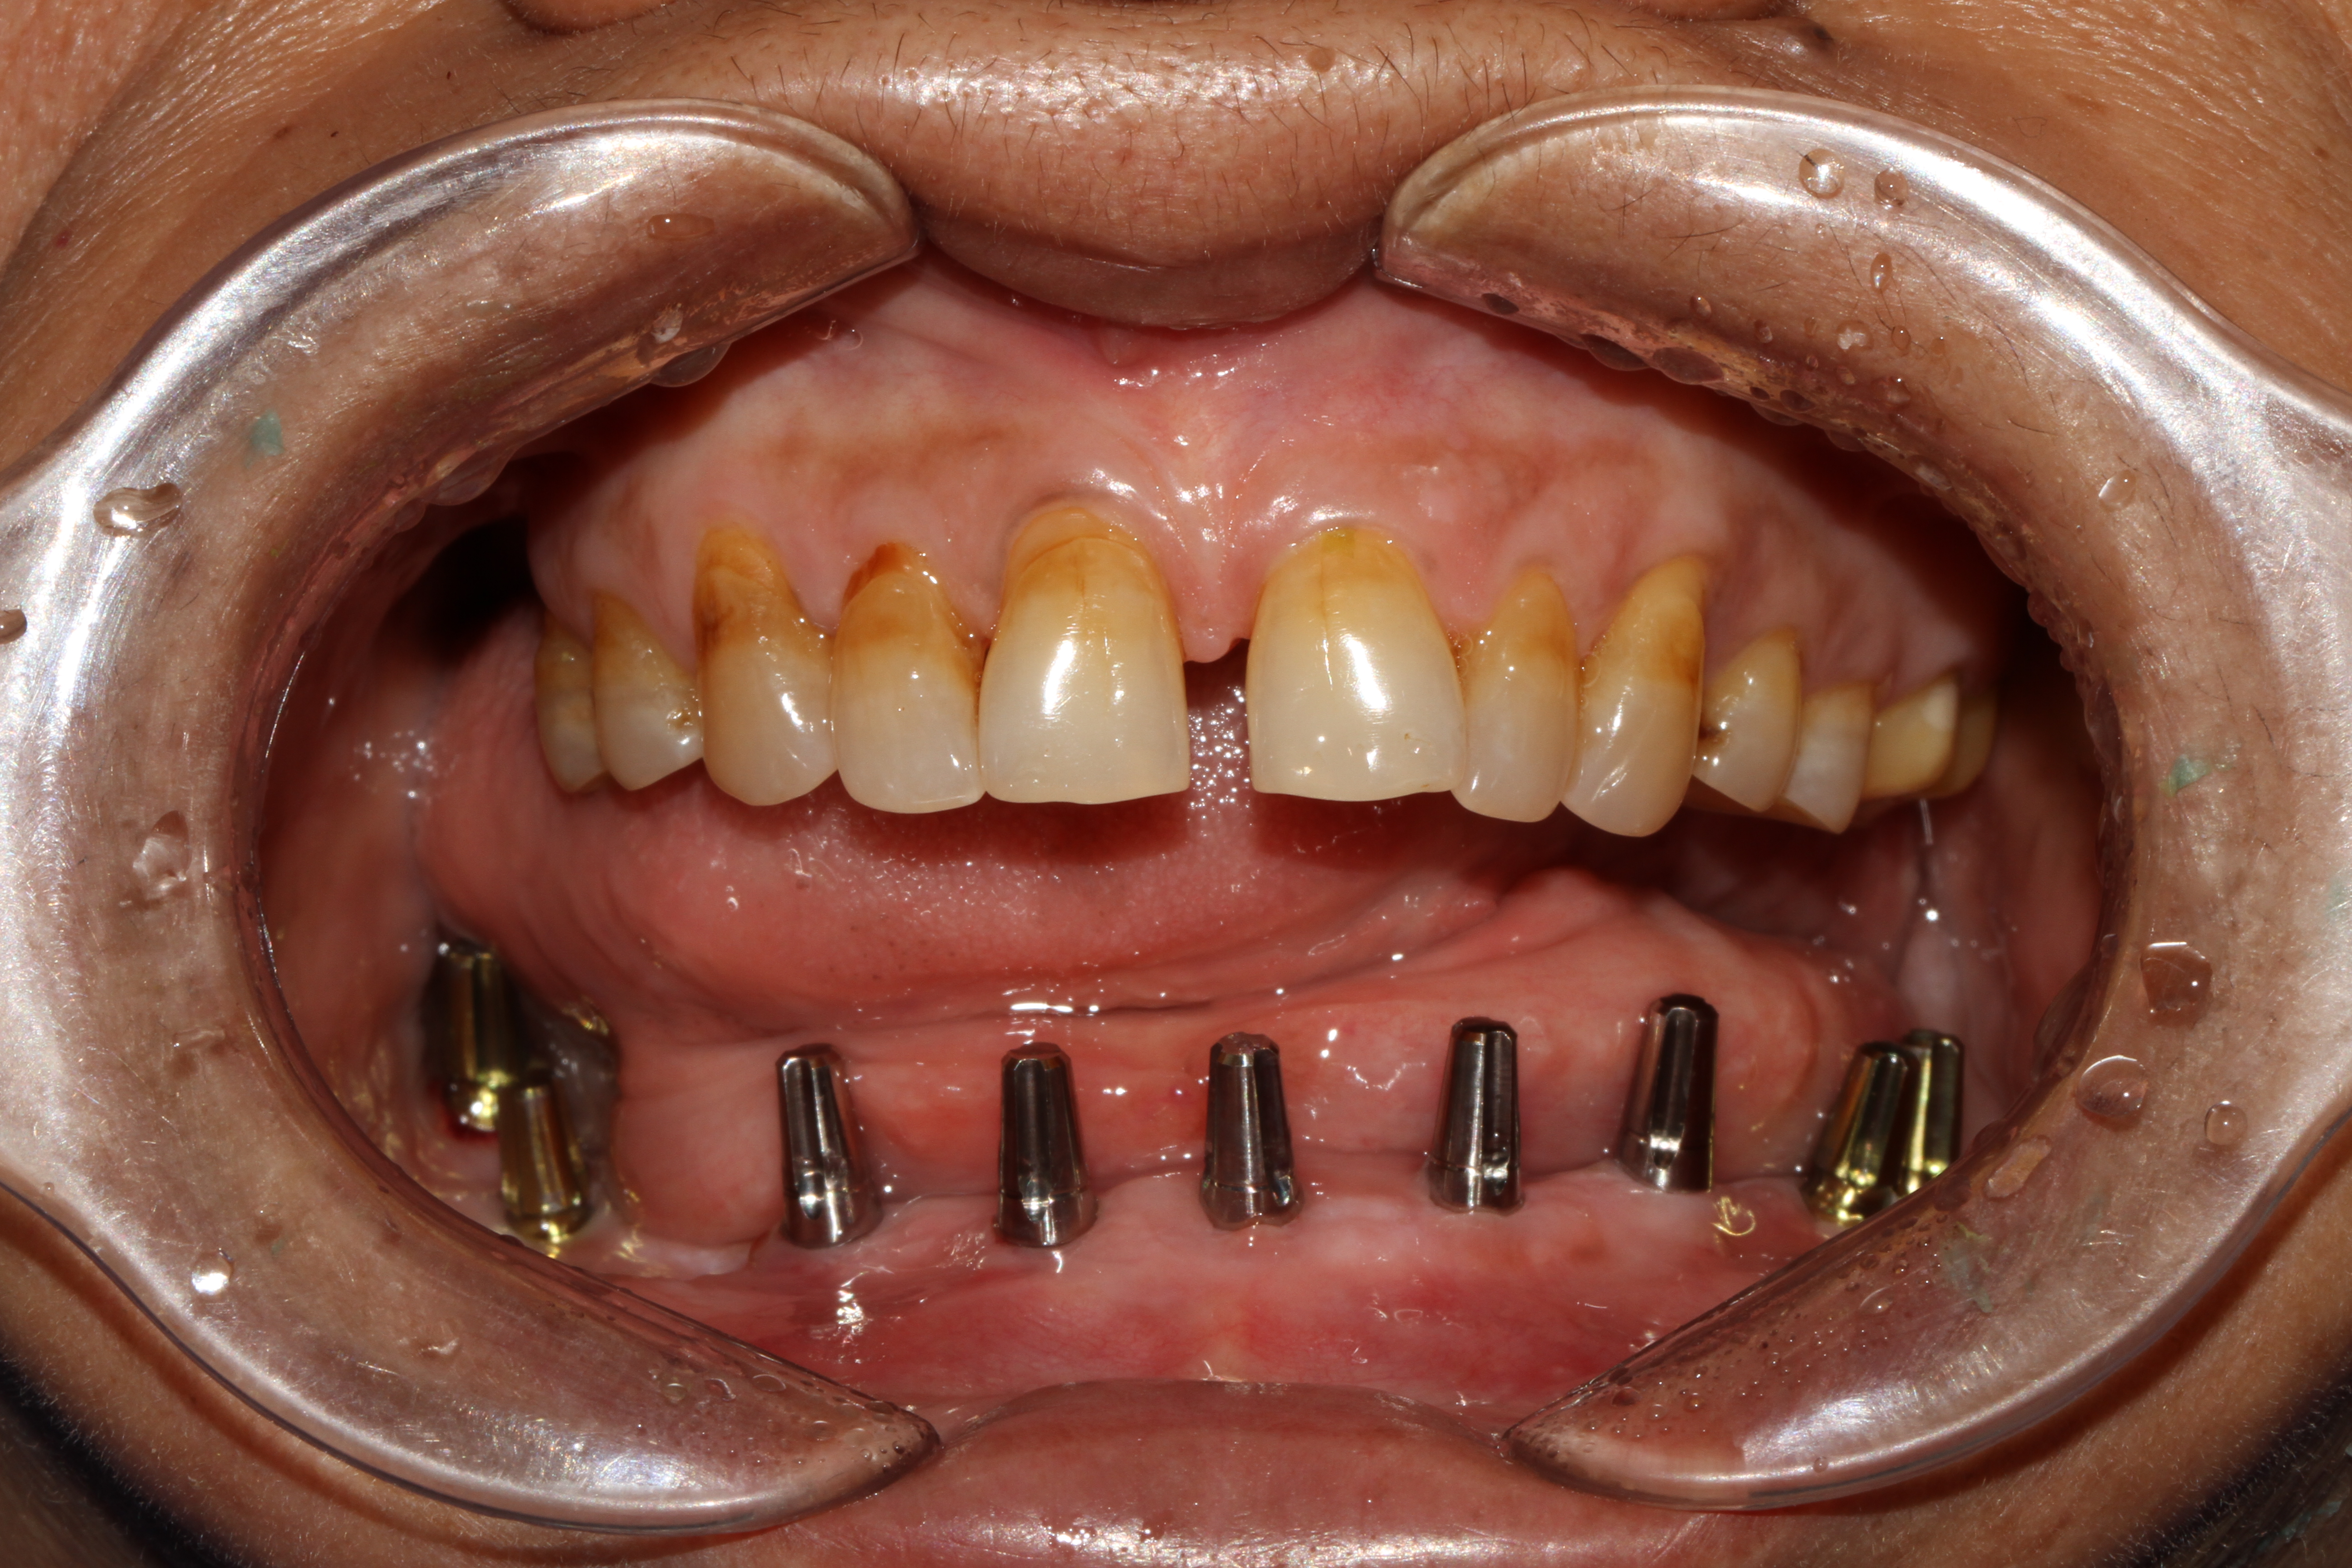

When it comes to replacing the entire arch of a lower jaw with 14 teeth, options like replacement with a zirconia crown, which is free of metal or porcelain fused to metal (ceramic) crown can be used. These crowns are fabricated in our hi-tech lab in 3 days which is fixed with the new generation of immediate loadable single piece implant. At Jani's Implant Cantre and Smile Studio, basal implants with a combination of crestal implants are used. Using this art of implant placement all 14 teeth which include the second molars are replaced. The introduction of second molars by this step will help the patient chew in a more efficient way similar to that of natural teeth. depending upon the patient's medical status, oral health and the quality of the bone, 6-8 implants are placed on which 14 teeth (full arch) is fixed. This is a full mouth immediate loadable implant therapy for the lower jaw. This is done in the form of permanent teeth in 3 days protocol where no bone augmentation and bone grafting is needed.